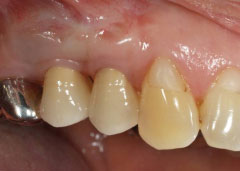

| 歯茎にプラーク(歯垢着が)と歯石の沈認められます。歯肉が腫れ、出血がありました。 | 歯科衛生士の治療と、ブラッシング技術の向上により、歯茎が引き締まり健康的な状態になりました。 | |